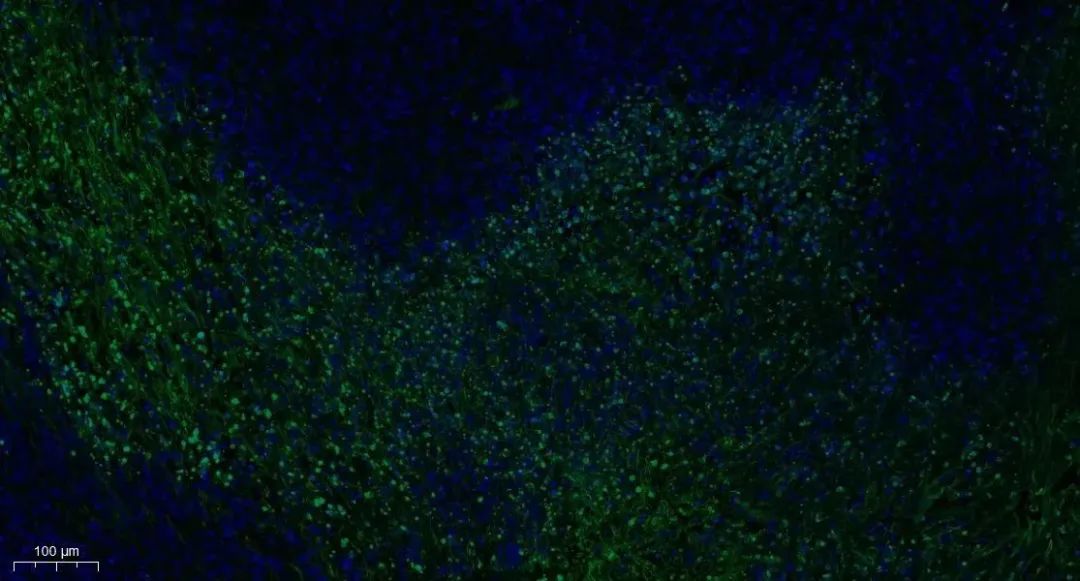

Tunel染色

细胞凋亡中, 染色体 DNA 双链断裂或单链断裂而产生大量的粘性 3'-OH 末端,可在脱氧核糖核苷酸末端转移酶(TdT)的作用下,将脱氧尿苷三磷酸核苷酸(dUTP)和荧光素形成的衍生物标记到 DNA 的 3'-末端,从而可进行凋亡细胞的检测,这类方法称为脱氧核糖核苷酸末端转移酶介导的缺口末端标记法。

由于正常的或正在增殖的细胞几乎没有 DNA 的断裂,因而没有 3'-OH 形成,很少能够被染色。由此,TUNEL 成为了检测 DNA 片段化(细胞凋亡)的最常用方法。

Tunel染色实例